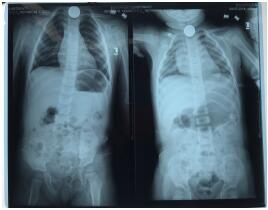

2名小孩誤吞的硬幣都卡在食管入口處,為食管第一狹窄部位,硬幣活動(dòng)度差,鏡身難以控制,取異物耗時(shí)長,患兒難以配合內(nèi)鏡操作,故需于麻醉狀態(tài)下進(jìn)行。由于嬰兒口腔及食道較成人狹小,最小的咬口也無法塞進(jìn)患者的口腔,醫(yī)務(wù)人員使用5ml注射撐開兒童的口腔,選擇纖細(xì)的支氣管鏡,在多次嘗試進(jìn)鏡后,將5角硬幣順利取出。